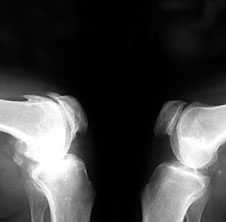

Ранние рентгенологические признаки (соответствуют 1–2 стадиям артроза по Kellgren):

1. Вытягивание и заострение краев межмыщелкового возвышения большеберцовой кости (в месте прикрепления крестообразной связки).

2. Небольшое сужение суставной щели (чаще в медиальном отделе сустава).

3. Заострение краев суставных поверхностей мыщелков бедренной и большеберцовой кости, чаще в медиальном отделе сустава (связано с большей нагрузкой на этот отдел сустава), особенно при наличии варусной деформации сустава; реже – в латеральной части или одновременно в обеих половинах суставной поверхности (рис. 2).

Рис. 2. Rо-графия коленных суставов в боковой проекции.

Артроз феморопателлярных суставов (больше слева). Артроз коленных суставов (I ст по Kollgren справа, IV ст. по Kollgren слева)

При прогрессировании артроза коленных суставов (соответствует 3–4 стадиям артроза по Kellgren):

• нарастает сужение суставной щели

• развивается субхондральный остеосклероз в наиболее нагруженной части сустава

• появляются множественные крупные остеофиты на боковых, передних и задних краях суставных поверхностей

• редко обнаруживаются субхондральные кисты

Вторичный синовит с развитием субпателлярной или подколенной кисты Бейкера:

• суставные поверхности бедренной и большеберцовой кости уплощаются, становятся неровными и теряют свою анатомо–функциональную дифференциацию

• многогранную неправильную форму преобретает сесамовидная кость (fabella)

• могут обнаруживаться обызвествленные хондромы

• редко возможно развитие асептических некрозов мыщелков костей.